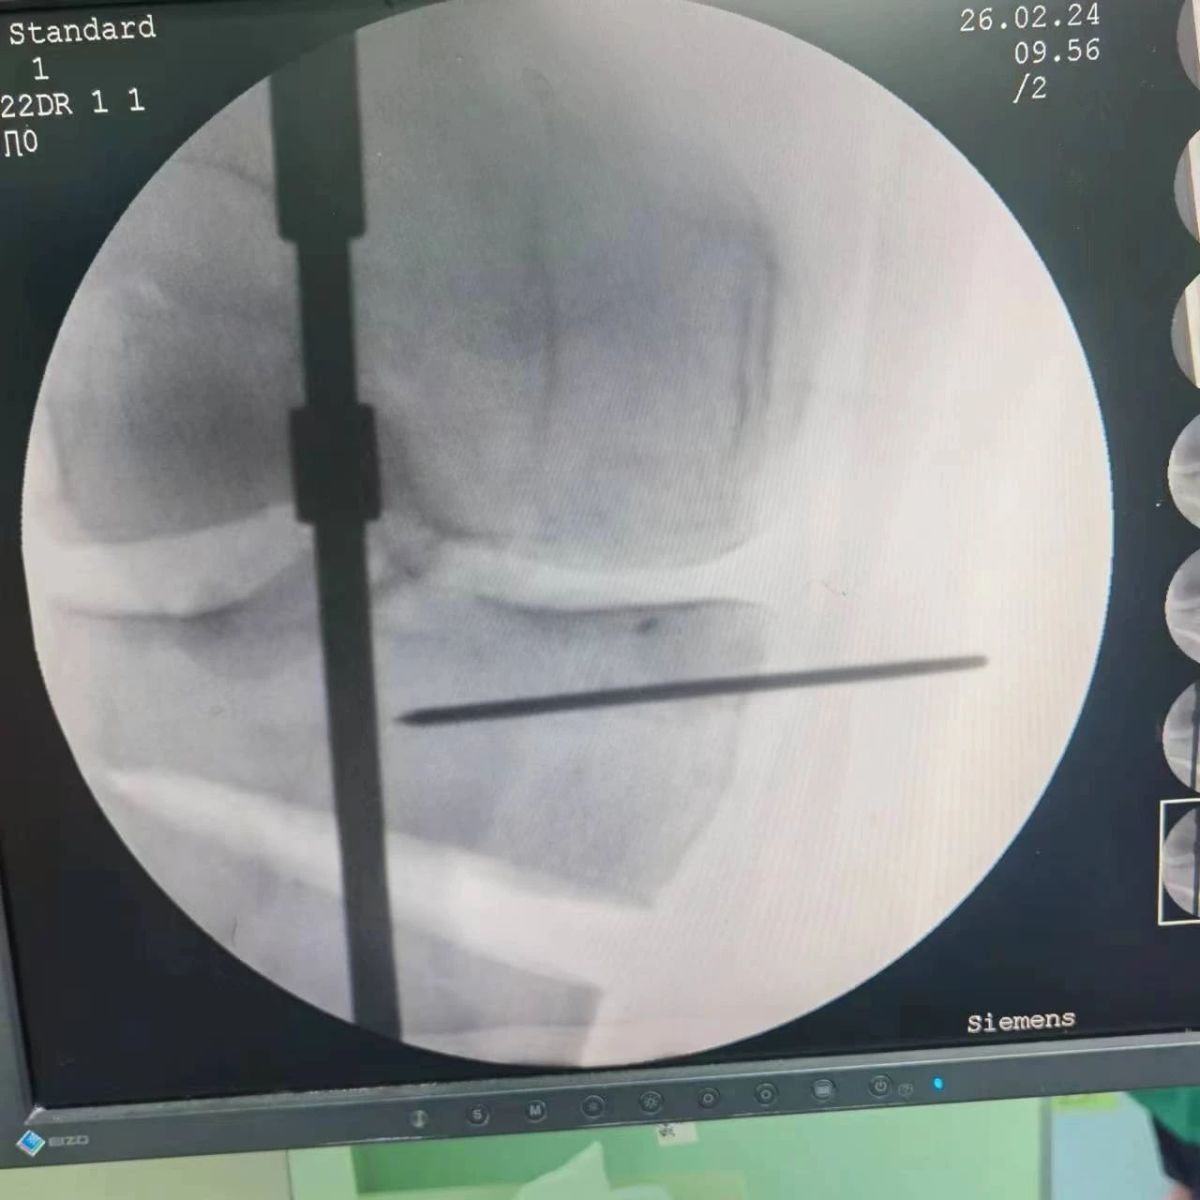

患者為一名45歲男性,查體及X片可見明顯的膝內(nèi)翻,內(nèi)翻畸形主要來源于脛骨近端,關(guān)節(jié)鏡下可見內(nèi)側(cè)間室軟骨全層磨損,疼痛較重,年紀(jì)輕輕幾乎喪失工作能力。對于這種日?;顒有枨蟊容^大的患者朋友,我們盡最大可能給予保膝治療,李付彬主任給患者詳細(xì)講解了保膝治療的方案(脛骨近端高位截骨)及預(yù)期效果,給患者帶來了極大希望。為了更精確、更微創(chuàng)的治療,李付彬主任團(tuán)隊(duì)緊跟國內(nèi)外科技前沿,采用計(jì)算機(jī)精準(zhǔn)術(shù)前規(guī)劃,并設(shè)計(jì)3D打印截骨導(dǎo)板,力求給患者帶來更精準(zhǔn)、更安全的手術(shù)效果。

李付彬主任團(tuán)隊(duì)通過精準(zhǔn)術(shù)前規(guī)劃,設(shè)計(jì)目標(biāo)力線及調(diào)整撐開角度,轉(zhuǎn)化成需要撐開的高度,最終設(shè)計(jì)出同等高度的填充塊,術(shù)中驗(yàn)證力線調(diào)整與術(shù)前規(guī)劃完全一致!

鋼板位置、螺釘位置及長度均可通過術(shù)前規(guī)劃計(jì)算,術(shù)中通過定位操作,基本與術(shù)前規(guī)劃一致,手術(shù)快速高效完成,外側(cè)合頁保留完整。無任何并發(fā)癥出現(xiàn)。術(shù)后見鋼板位置及力線糾正近乎完美!